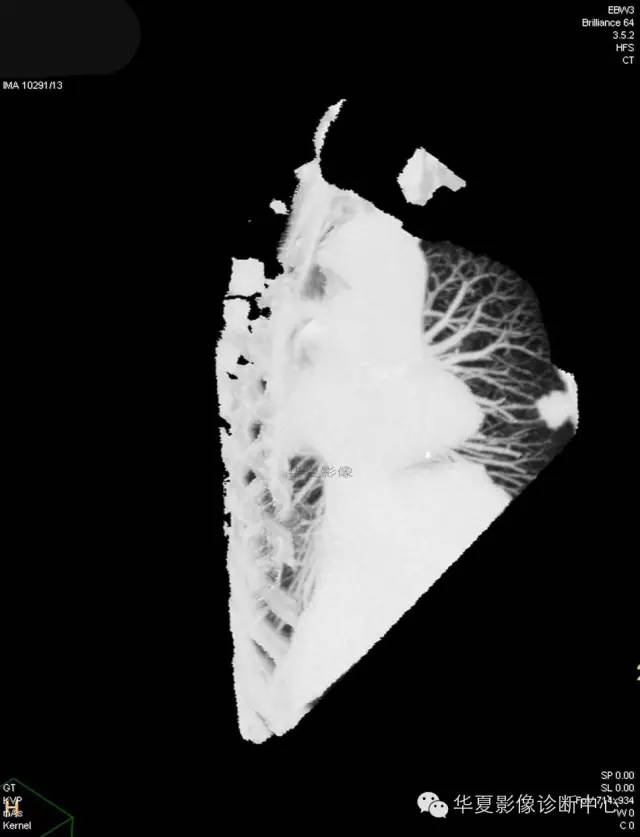

【病例学习】典型周围型肺癌CT病例一例

女,56岁,其父因肺癌去世,自觉胸部疼痛不适来诊要求拍胸片。

1.右肺上叶:肺组织1块,大小13×4×7cm。切面棕红色。2.右肺上叶肿物:灰白色组织一块,大小3×1×1.5cm。切面灰白色。3.右肺中叶结节:灰白色绿豆大组织1块。4.淋巴结:灰黑色绿豆大组织1块。

(右)肺中分化鳞状细胞癌。浸及胸膜。支气管残端切净。淋巴结未见癌转移(0/10)。